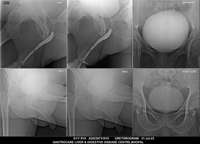

Section: URETHROGRAM

Total: 95 Cases